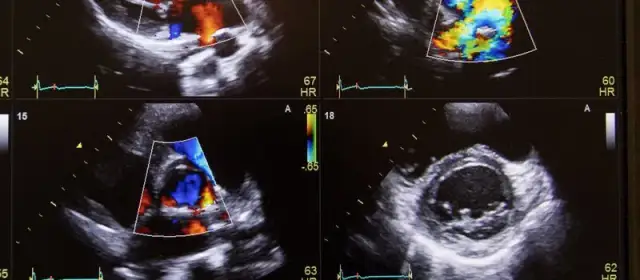

Ultrasonografia jajników: co pokazuje i jak jest przeprowadzana

Ultrasonografia przezpochwowa to kluczowe badanie stosowane w diagnostyce zespołu policystycznych jajników (PCOS). Procedura polega na wprowadzeniu specjalnego czujnika do pochwy, co pozwala na uzyskanie wyraźnych obrazów jajników i macicy. Badanie to jest nieinwazyjne i trwa zazwyczaj od 15 do 30 minut, a jego wyniki są dostępne od razu po zakończeniu. Dzięki ultrasonografii lekarze mogą ocenić strukturę jajników, co jest istotne dla diagnozy PCOS.Podczas badania ultrasonograficznego oceniane są m.in. obecność pęcherzyków jajnikowych oraz ich rozmiar. W przypadku PCOS, charakterystyczne jest występowanie co najmniej 12 pęcherzyków o średnicy od 2 do 9 mm lub zwiększenie objętości jajnika do powyżej 10 cm³. Obraz ultrasonograficzny może również wykazywać inne nieprawidłowości, które mogą pomóc w postawieniu diagnozy. Warto zaznaczyć, że ultrasonografia jest jednym z najskuteczniejszych narzędzi w wykrywaniu PCOS i monitorowaniu stanu zdrowia pacjentek.

Kryteria oceny policystycznych jajników w ultrasonografii

Diagnostyka PCOS opiera się na określonych kryteriach oceny jajników podczas ultrasonografii. Zgodnie z kryteriami rotterdamskimi, do rozpoznania policystycznych jajników konieczne jest spełnienie przynajmniej dwóch z trzech warunków: obecność policystycznych jajników, zaburzenia cyklu menstruacyjnego oraz objawy hiperandrogenizmu. Podczas badania ocenia się liczbę pęcherzyków oraz ich rozmiar, co jest kluczowe dla postawienia diagnozy. W przypadku PCOS, lekarze szukają co najmniej 12 pęcherzyków w jednym jajniku lub zwiększonej objętości jajnika.